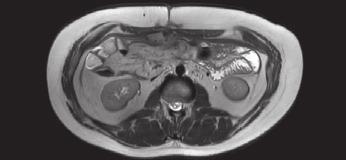

Muž, narozen v roce 1999, s rodinnou anamnézou familiární adenomatózní polypózy u matky s potvrzenou mutací APC genu. V roce 2017 byly u nemocného zjištěny mnohočetné adenomy v tlustém střevu v řádu stovek a také několik drobných adenomů v duodenu. V roce 2018 byl vyšetřen z důvodu rychle se rozvíjející neurologické symptomatologie v podobě závratí a silných bolestí hlavy. Vyšetření prokázalo expanzivní proces v zadní jámě lební, později verifikovaný jako meduloblastom. Ve stejném roce se pacient podrobil neurochirurgickému výkonu s odstraněním nádoru a konstrukcí ventrikulo-peritoneálního shuntu. Následovala adjuvantní aktinoterapie v podobě protonové léčby a chemoterapie. V roce 2020 byl podrobně neurologicky a onkologicky vyšetřen se závěrem kompletní remise nádorového onemocnění. V této době nastal vhodný okamžik vyřešit adenomatózu tlustého střeva, a proto bylo provedeno celkové přešetření stavu včetně magnetické rezonance břicha (obr. 1). V dubnu 2021 ve věku 22 let se podrobil laparoskopické subtotální kolektomii a vytvoření ileo-rektální anastomózy (obr. 2). Tento typ výkonu byl preferován před restorativní proktokolektomií s ileopouch-anální anastomózou pro relativně nižší počet adenomů v rektu a v distálním sigmatu. Operace proběhla bez komplikací a pacient se velmi rychle po operaci zotavil. V resekátu tlustého střeva byly nalezeny stovky menších polypů velikosti do 20mm, bez průkazu karcinomu. V srpnu 2021 odcestoval na dlouhodobý studijní pobyt do Dánska. Bohužel již v září

Obr. . Magnetická rezonance v roce . (Zdroj: prim. MUDr. Adam Pavli ko, Klinické centrum ISCARE a.s).

Fig. . Magnetic resonance imaging in . (Source: Adam Pavli ko, MD, Clinical Centre ISCARE a.s.).